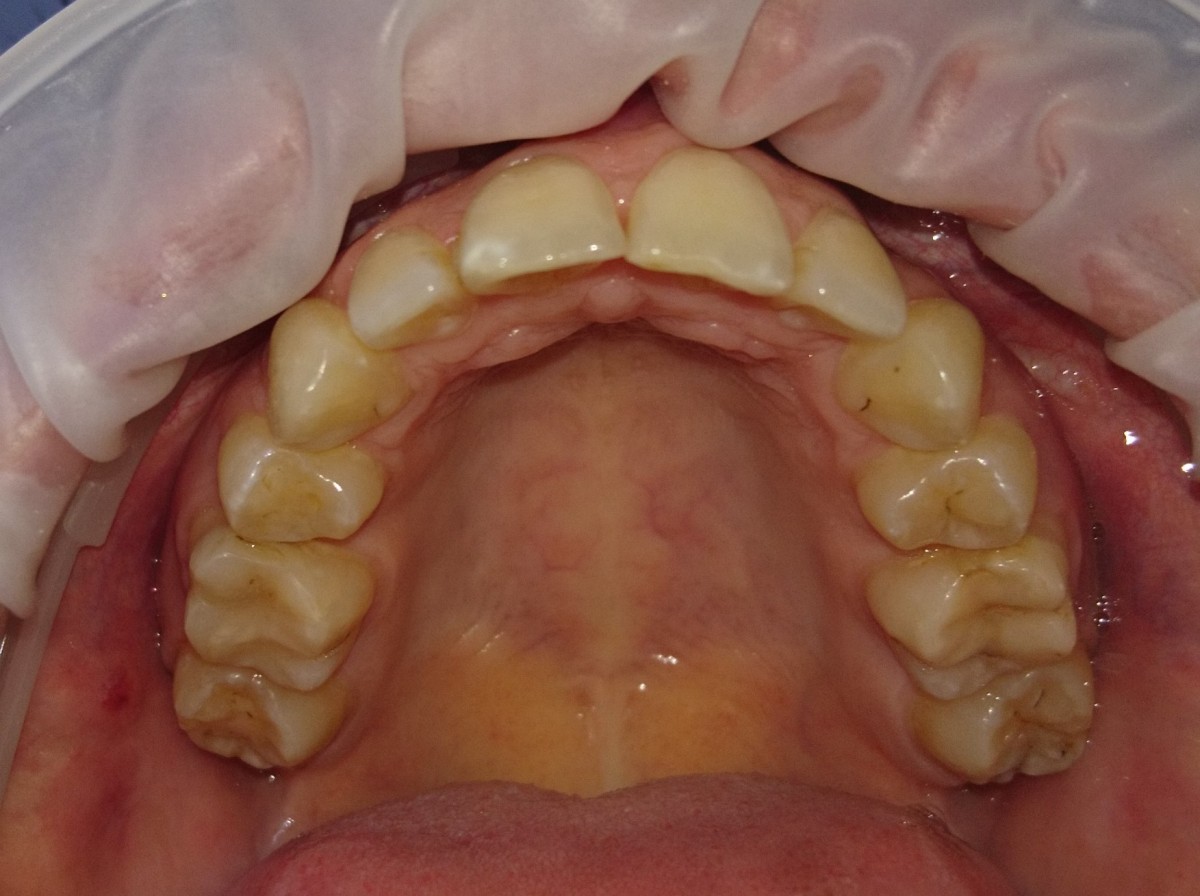

Pacient 23 ani. Extracție 1.4, 2.4, 3.5, 4.5, aparat ortodontic fix ceramic.